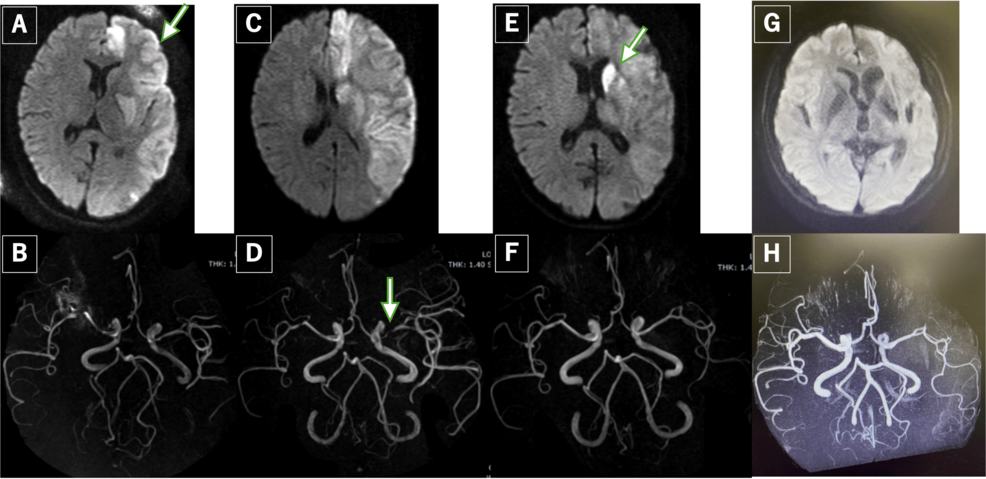

The patient, a 34-year-old woman, initially presented with severe headaches and visual disturbances on October 26, 2023. Neurological examination revealed no focal deficits, but imaging studies confirmed the presence of RCVS, characterized by diffuse segmental vasoconstriction of cerebral arteries. Simultaneously, laboratory tests indicated low levels of free thyroxine (T4) and normal thyroid-stimulating hormone (TSH), a pattern indicative of central hypothyroidism. Further investigation revealed a mildly enlarged pituitary gland on MRI.

Treatment for RCVS typically involves managing blood pressure and preventing further vasoconstriction. The patient was administered intravenous calcium channel blockers, and her headaches gradually resolved over the following days. Concurrently, she was started on levothyroxine replacement therapy for the central hypothyroidism. Remarkably, both conditions showed significant improvement with treatment. Repeat imaging on November 8, 2023, demonstrated resolution of the cerebral vasoconstriction, and thyroid hormone levels normalized with levothyroxine.